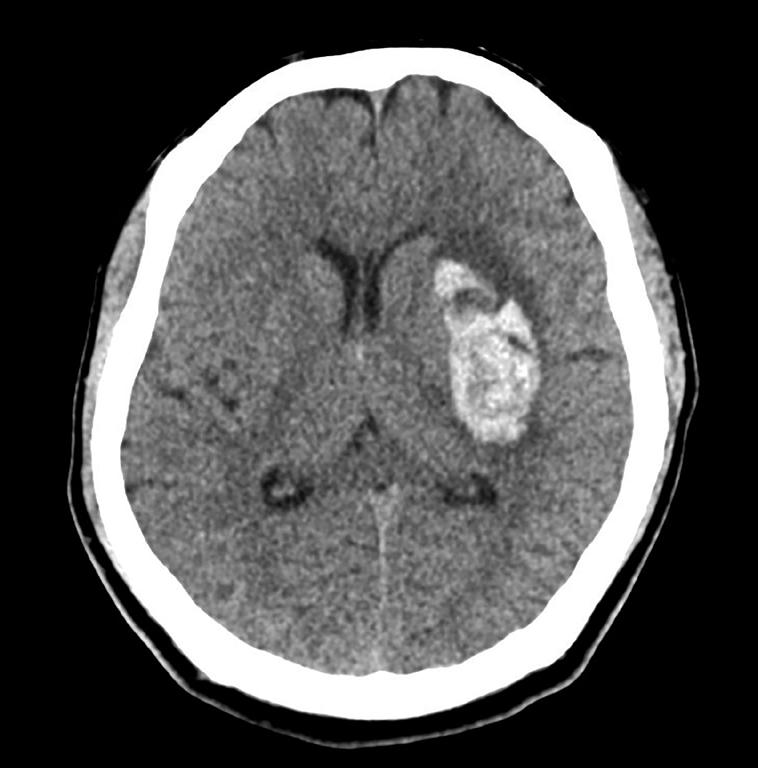

Hjerneslag er blålys-medisin, og ved mistenkt hjerneslag skal pasienten hurtig transporteres til nærmeste

sykehus. Vi kan ikke skille mellom hjerneslag forårsaket av blodpropp eller blødning ved klinisk undersøkelse. Rask bildeundersøkelse er derfor avgjørende for valg av videre behandling, og CT caput inkludert CT angiografi er førstevalg av billedmodalitet i akuttfasen. Hos en pasient med hjerneblødning bør CT angiografi av de intracerebrale karene utføres for å påvise eventuelle underliggende strukturell karpatologi som utløsende årsak. En lekkasje av kontrastmiddel inn i hematomet («spot sign») tolkes som fortsatt pågående blødning og er en prognostisk viktig faktor for et dårligere utkomme. I tilfeller der blødingslokalisasjon ikke følger de vanlige arterielle kargebetene anbefales det å legge til kontrast i venefase for å utelukke sinusvenetrombose. (Figur 1)

Figur 1. CT caput. Blødning i basalganglier ve side med tilstøtende ødem og lett kompresjon av ve sideventrikkel. Marginal midtlinje forskyvning. (Fra Shutterstock, med tillatelse)

National Institutes of Health Stroke Scale skår (NIHSS)>5, og premorbid funksjonsnivå mRS 0-1) (26). Resultatet var i hovedsak positivt for de med overfladisk kortikale blødninger, og ikke ved en dyp blødning slik vi har vist i Figur 1. Studien bestod som vi ser over av en svært selektert pasient gruppe, der man screenet over 11 000 for å inkludere 300 pasienter. I en annen nylig studie så man en trend mot økt overlevelse ved kirurgisk dekompressiv kraniektomi uten hematom evakuering ved alvorlige dype subkortikale blødninger, uten at de ble operert på vital indikasjon (27). Hva slags klinisk betydning studiene får gjenstår å se, men inntil videre rådes det til å konferere med nevrokirurg ved akutte hjerneblødninger, og sammen diskutere muligheter og nytten ved kirurgi.